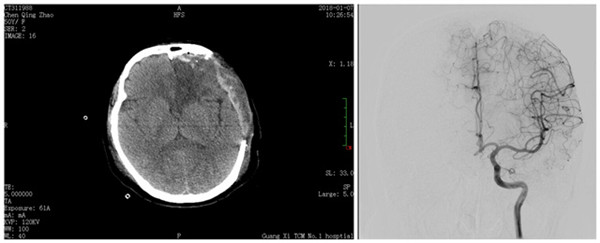

在颅脑外科及手术麻醉科团队的积极共同努力下,精细显微手术操作,完整切除巨大畸形血管团,顺利清除颅内血肿。术后瞳孔恢复3mm,对光反射灵敏,呼唤睁眼,能配合查体。术后在颅脑外科重症监护室继续救治,运用中西医结合疗法,经过30余日的精细治疗及护理,目前患者不仅脱离了生命危险,更能生活自理、行动自如。近日行全脑血管造影检查,显示畸形血管团已消失,疾病得到了根治。患者从命垂一线到逐渐完全恢复生活状态,语言正常,能独立行走。

术后影像